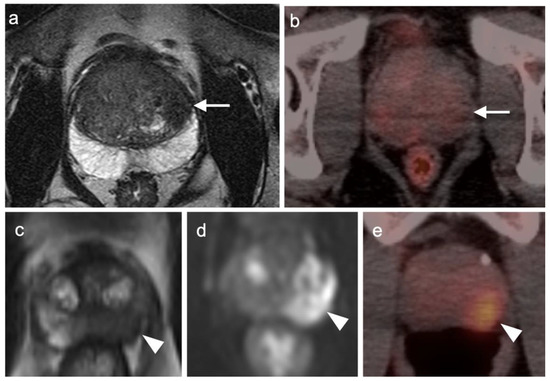

3.1. Prostate Cancer

3.2. Urothelial Carcinoma

3.3. Primary Testicular Cancer